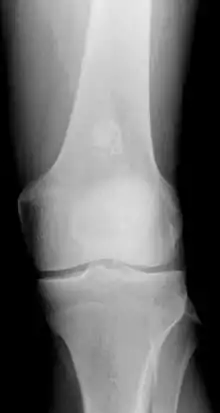

الورم الغضروفي الباطن (بالإنجليزية:Enchondroma) عبارة عن كيسة غضروفية في نخاع العظام تُكتشف أثناء التصوير بالأشعة السينية ولديها مظهر مميز أتناء التصوير بالرنين المغناطيسي

- تصوير بالأشعة السينية، قد يوجد أورام في أي عظمة نشأت من غضروف. تكون عبارة عن آفات تحللية والتي تحتوي عادة على مطرس غضروفي متكلس ( في صورة أقواس ودوائر )، ما عدا في الأنامل. قد تكون مركزية أو متطرفة، نابضة أو غير نابضة.

قد يكون من الصعب التفريق بين الورم العظمي الباطن و احتشاء عظمي في فيلم التصوير بالأشعة السينية.